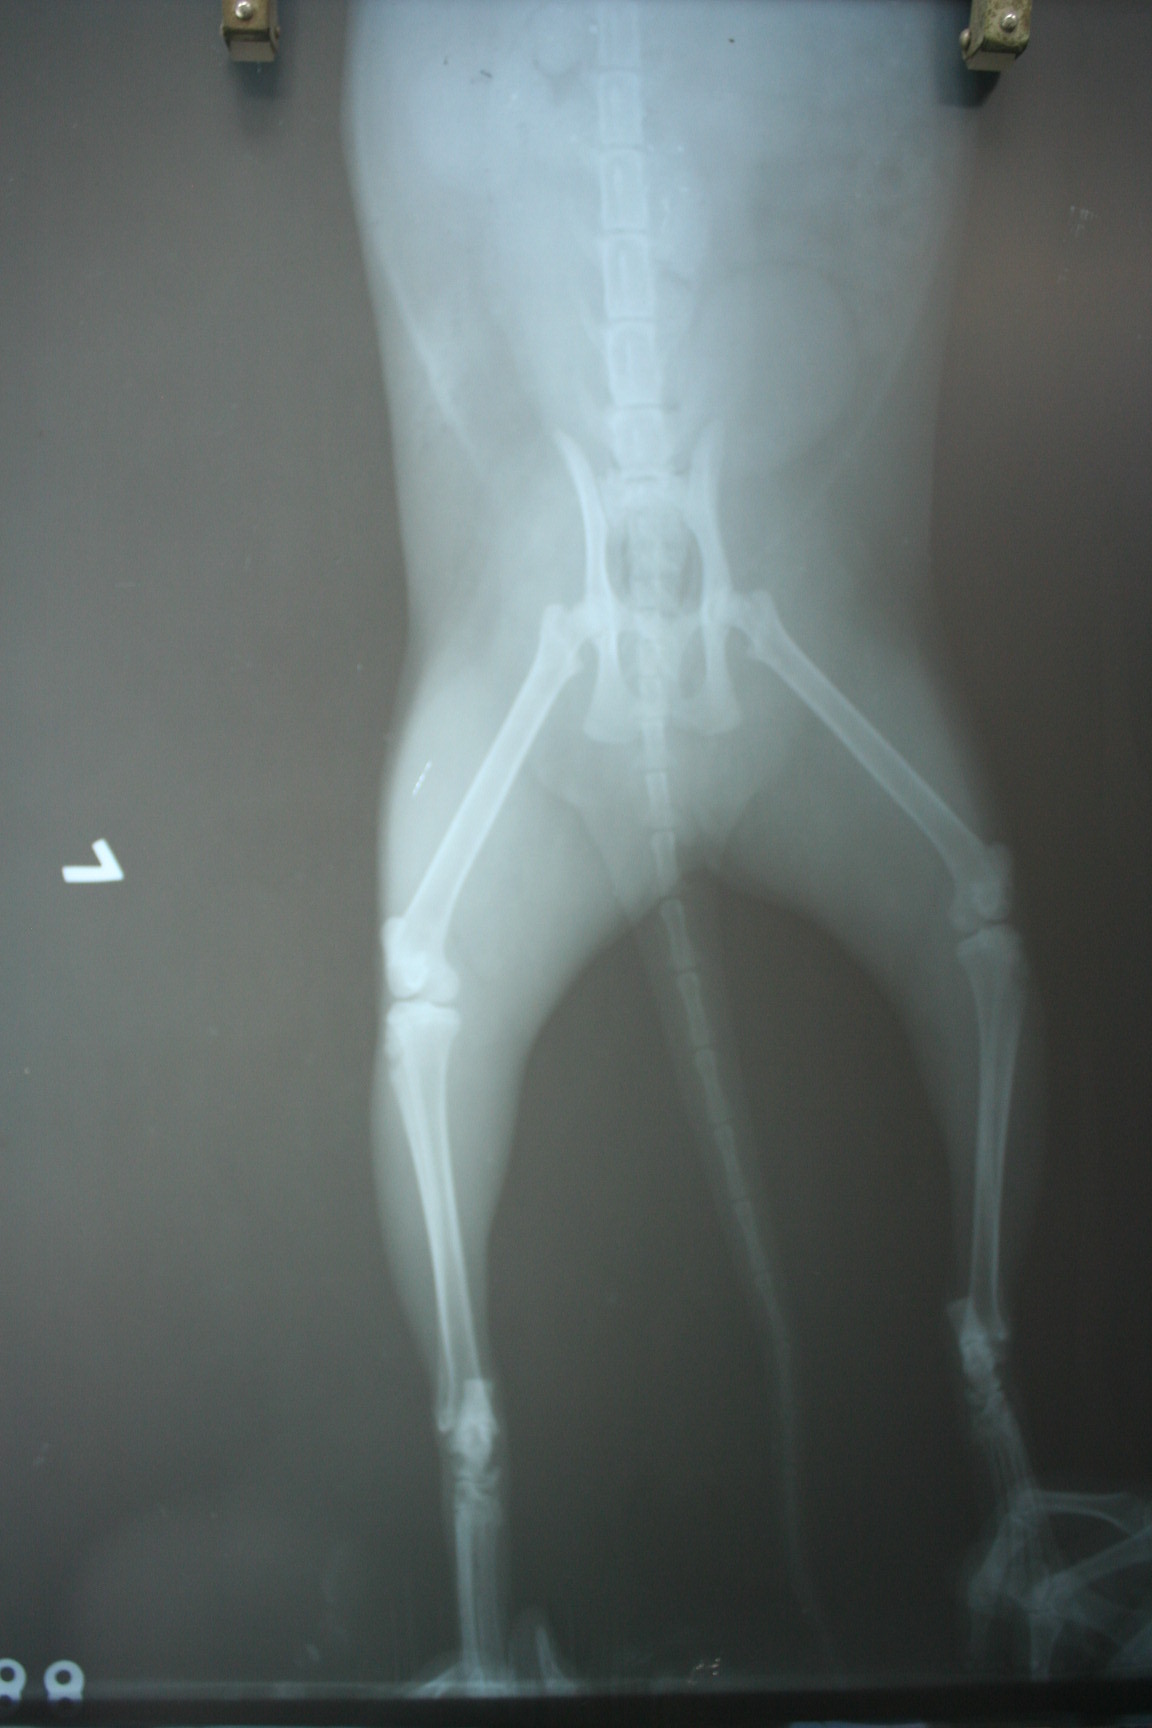

經醫生細心檢查發現,

小朋友除了左前及左後腿跛行外,

她的腳墊只剩一點點.

肌肉及肌腱也有受傷...

2. 10/14 X光片2張 800